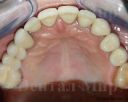

3. Слепки и 3Д сканирование зубов;

Протезирование зубов верхней челюсти